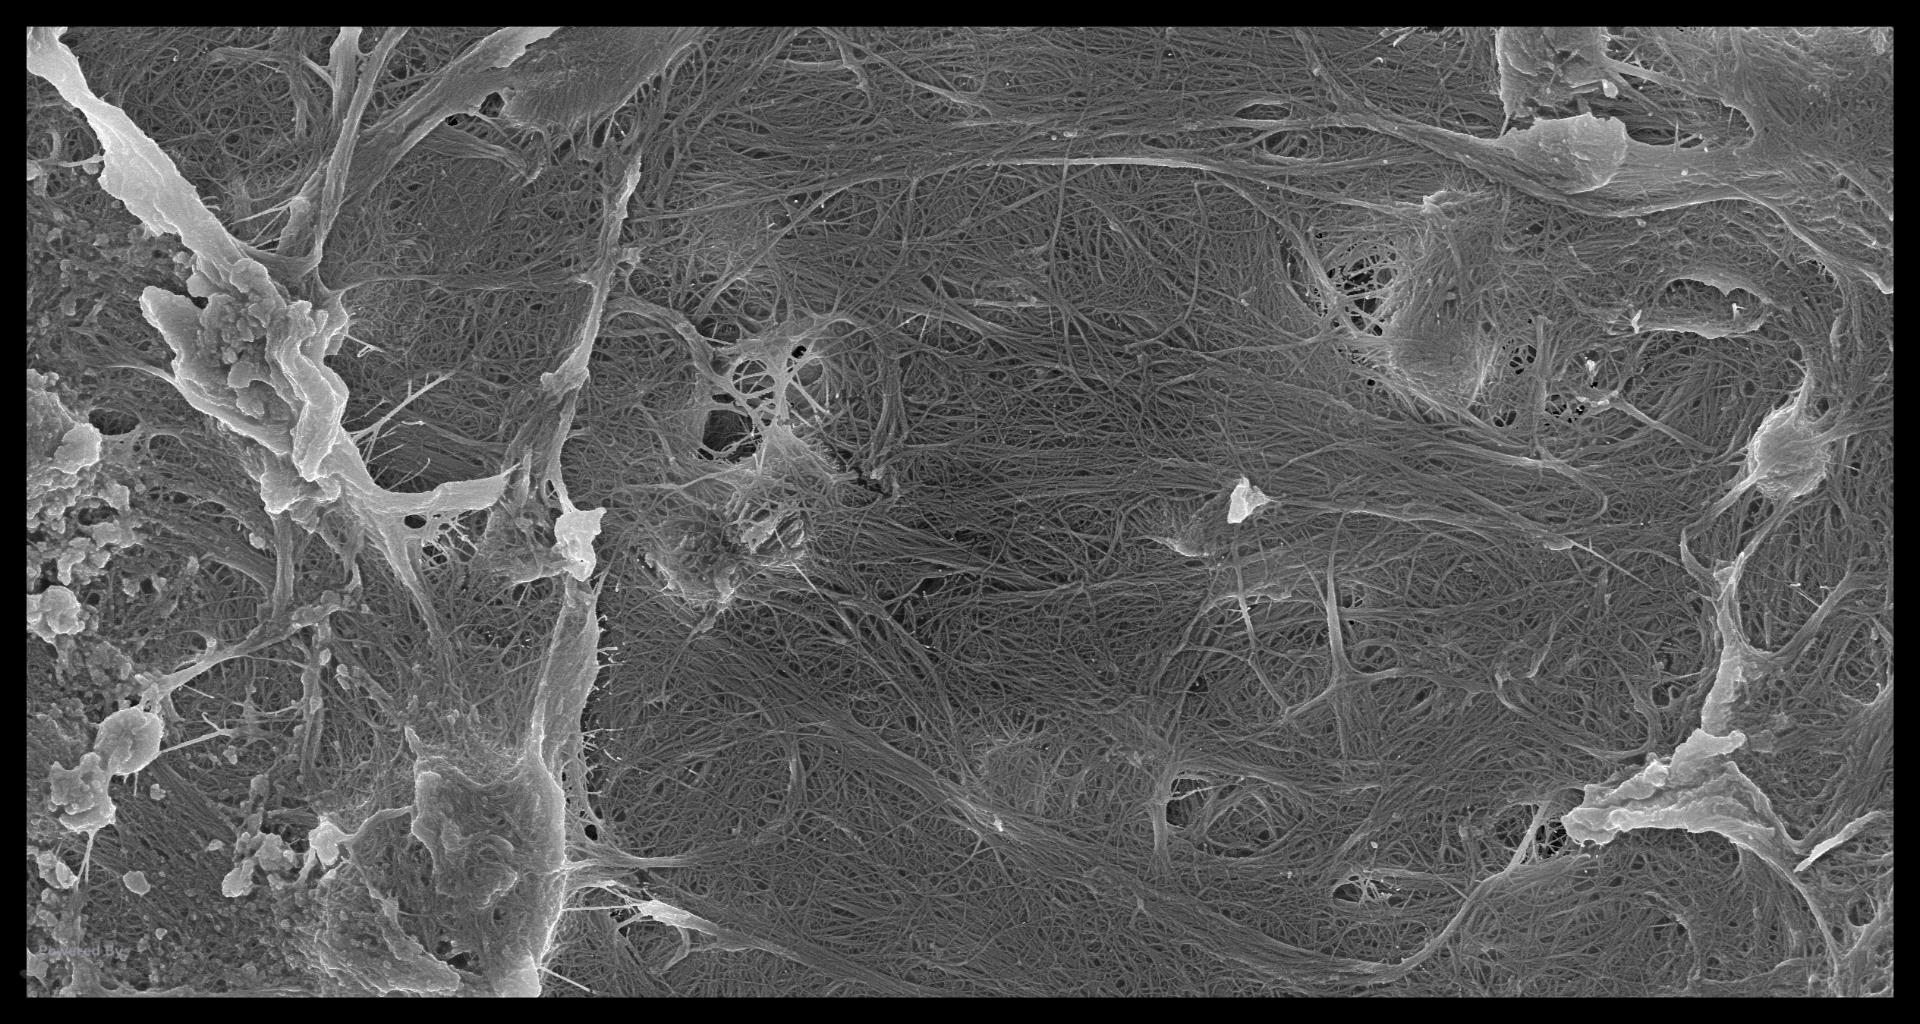

In looking at the GW effect, I did some preliminary work in trying to see the effect of EDTA and NaOCl on dentin—something I was only remotely familiar with. Anyway, just from a scientific perspective, when you decalcify dentin at various time frames, you can see how the collagen protein itself must act as the nucleation site for the apitite crystal to form. Although Ca and Phosphorus are present in the extracellular fluid, the actual orgaizing of the apitite structure appears to be controlled by the spacial structure of the collagen molecule. In the various stages of decalcification you can see here, it is clear the collagen must be controlling the process and you can see the calcospherites almost forming before your eyes. Probably not of great interest to a lot of endodontists but to me…. Always fascinated by the unique structure of dentin…. gbc